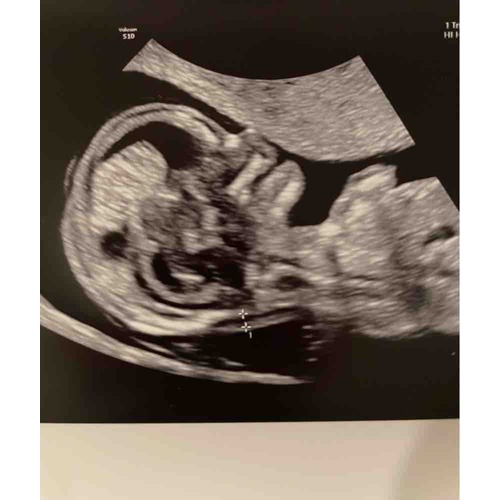

Iemand een idee?😁

Iemand die een gokje durft te wagen! 💙💖

💙💙

💖💖💖